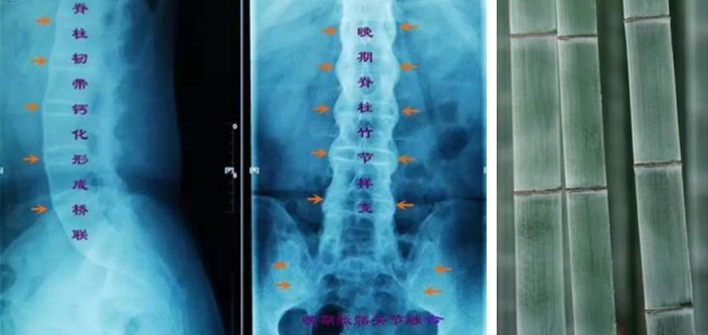

强直性脊柱炎的病因至今没有研究清楚,从流行病学调查发现,和遗传及环境因素关系密切。已经证实的是,该病和人类白细胞抗原(HLA-B27)密切相关,并有明显的家族聚集倾向。晚期的典型表现为“竹节样改变”。

- 晚期可出现严重的脊柱畸形(如上图)。